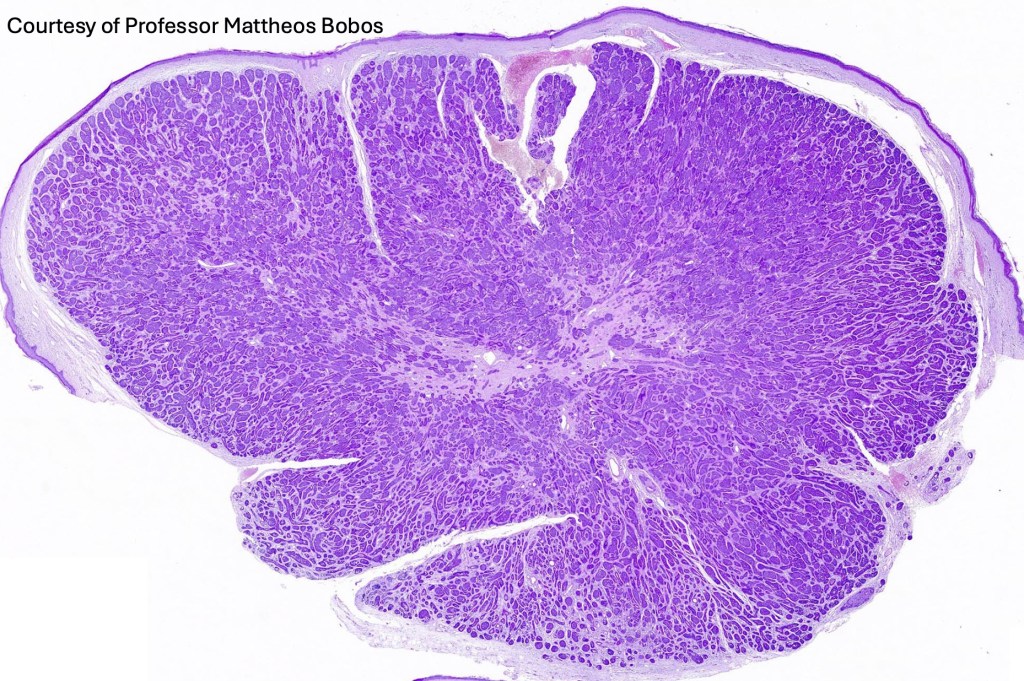

Histological features

•Dermal based

•Jigsaw/mosaic pattern arrangement of variably sized lobules of tumor cells with surrounding think, eosinophilic hyaline basement membrane

•Intralobular hyaline basement membrane material droplets

•Outer layer of intensely basophilic small cells surrounding larger central cells with pale staining or eosinophilic cytoplasm & vesicular nuclei

•Ductal differentiation